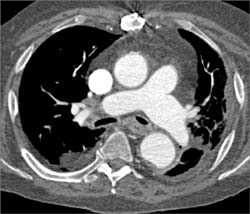

Diagnosis

Sites of Failed Bypass